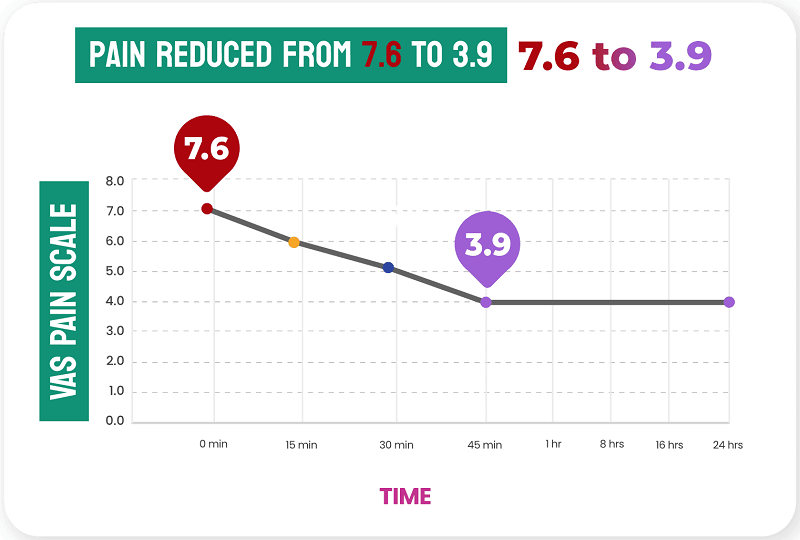

Infused with a powerful blend of active ingredients, this treatment penetrates deep into the affected area. It delivers fast-acting relief directly to the pain point, leaving you with a soothing sensation that works wonders.

Effectively tackles pain root causes by reducing swelling and inflammation. By addressing these issues, this treatment promotes faster healing and long-lasting relief.